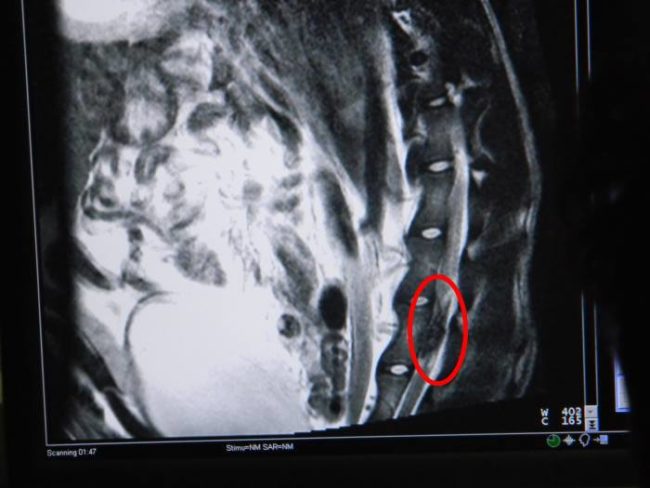

After that, on February 23, 2013, a monster shot at Zhile and many other dogs, and the horrific act of abuse led to his paralysis.

Veterinarian Marin Velickovski took the bullet out of his back. It was then that Zhile began the journey to health and happiness, but sadly, it became clear that he’d never walk without a rear-leg wheelchair again.